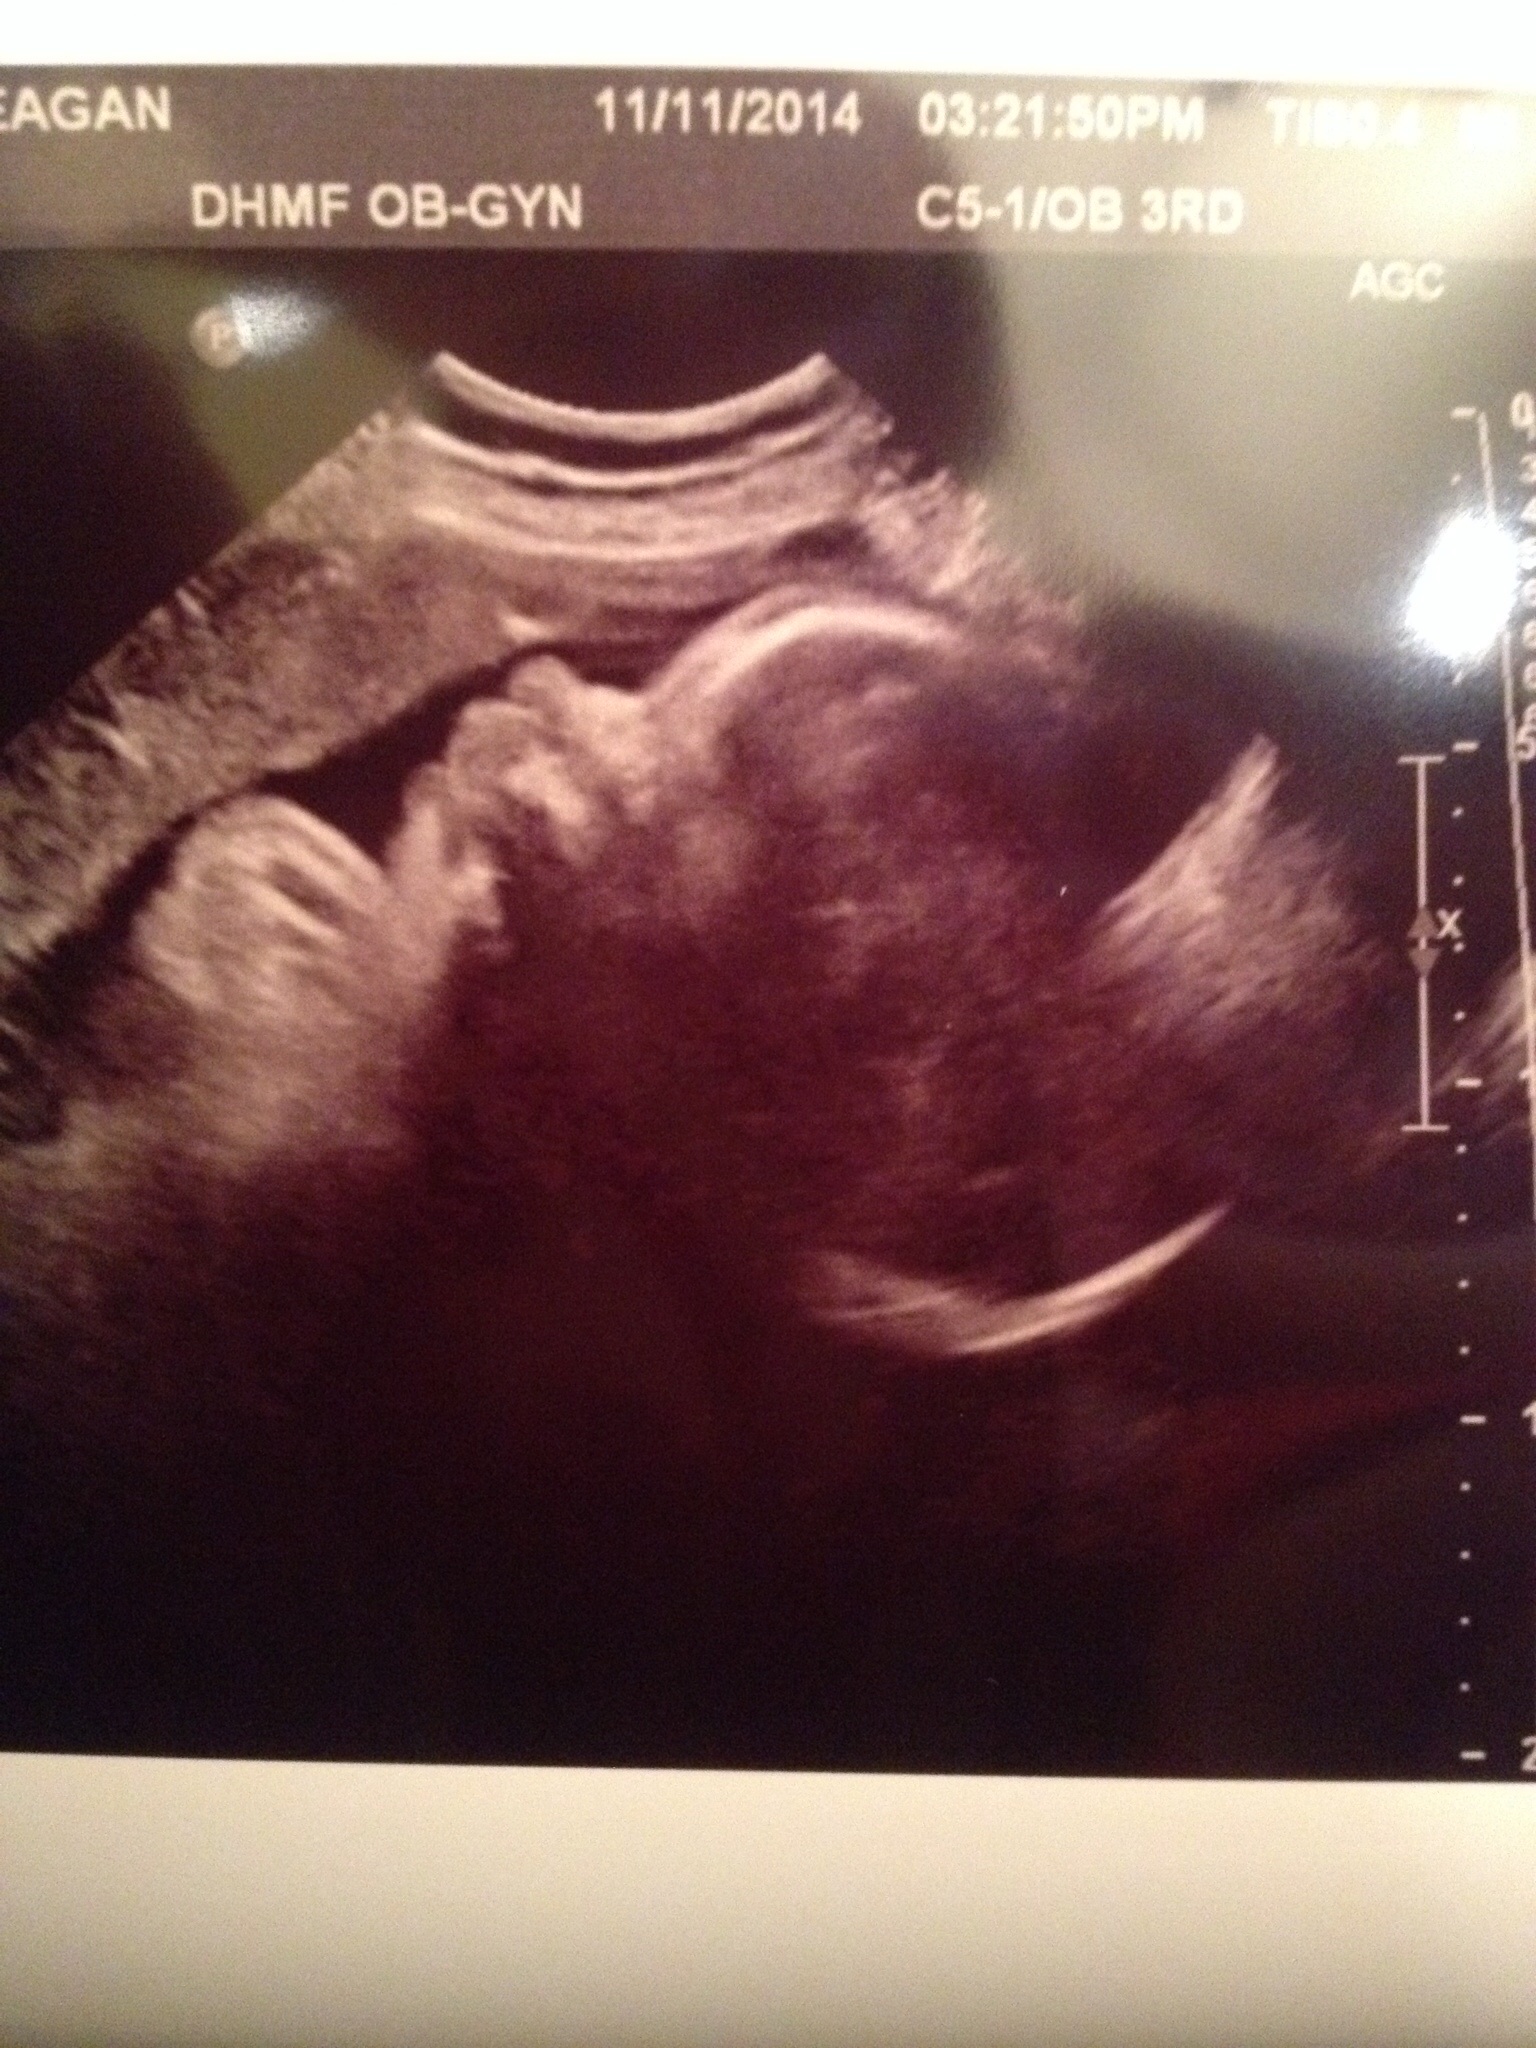

Hi all - I just had my 36 week check up and baby girl is looking a-okay! She's head down, facing the right way at the moment

And she may be a BIG baby. The estimate right now is that she's already 7.5 pounds, and she has a big head. Eeps! I'm reminding myself it's just an estimate, but holy smokes it is makin everything seem very real!